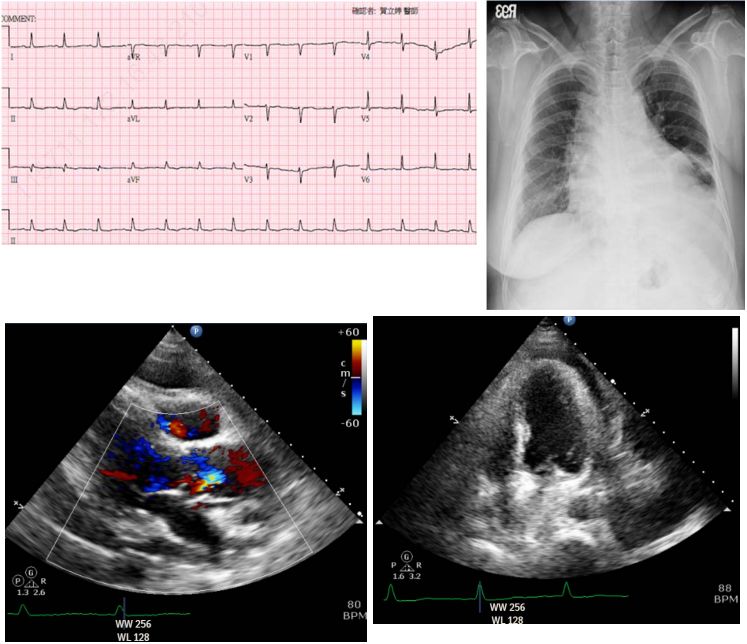

8. 86歲老太太因有二小時的胸悶前往醫院急診求治。病人在十年前因急性心肌梗塞而住院,在左前降支冠狀 動脈(Left anterior descending artery)置放冠狀動脈支架。病人尚有類風濕關節炎及老齡失智診斷。理學 檢查發現:BH:156 cm, BW:48 kg;BMI:19.7 kg/m²;T/P/R:36.2/66/22;BP:158/90 mmHg;在急診的其他檢驗尚無重大異常,其系列的生化檢驗、Chest X ray、心電圖如附圖:

(A) 高血壓性心臟病 (B) 左迴旋冠脈栓塞之Non-STE acute myocardial infarction (C) 左前降支冠脈栓塞之Non-STE acute myocardial infarction (D) 左前降支冠脈栓塞之STE acute myocardial infarction (E) 左迴旋冠脈栓塞之STE acute myocardial